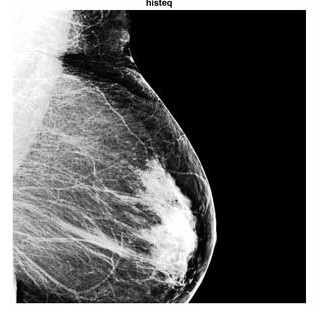

ماموگرافی نوعی تصویربرداری از سینه است که با دوزهای بسیار کم اشعه ایکس گرفته میشود و در تشخیص توده های خوش خیم و بدخیم پستان بسیار کمک کننده است. ماموگرافی سرطان پستان را ده سال زودتر از زمانی که توده قابل لمس باشد تشخیص می دهد. عوارض ماموگرافی ناشی از رادیواکتیو به مقدار بسیار ناچیز است.

شبیه سازی مقاله بهبود تصاویر دیجیتال ماموگرافی در متلب. فایل نرم افزاری پروژه پردازش تصویر ماموگرافی در اختیار شما قرار خواهد گرفت.

ماموگرافی یک عکس رادیوگرافی ساده از پستان و ابزاری برای کشف زودرس سرطانهای غیرقابل لمس پستان است. ماموگرافی میتواند سرطان پستان را ده